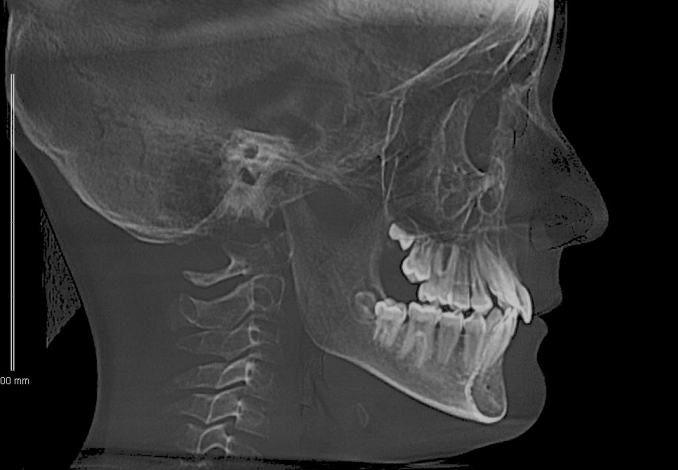

На ТРГ головы в боковой проекции - ретроположение верхней и нижней челюсти в сагиттальном направлении без нарушения размеров апикальных базисов и их взаиморасположения. Тип роста – нейтральный. Дентоальвеолярный анализ характеризует изменение инклинации резцов на верхней и нижней челюсти с незначительным дентоальвеолярным удлинением. На нижней челюсти в области боковой группы зубов определяется зубоальвеолярное укорочение, что характеризует формирование глубокой кривой Spee на данном этапе формирования прикуса постоянных зубов. (рис.3.)

Рис. 3. КЛКТ и ТРГ головы в боковой проекции пациента А. до лечения.